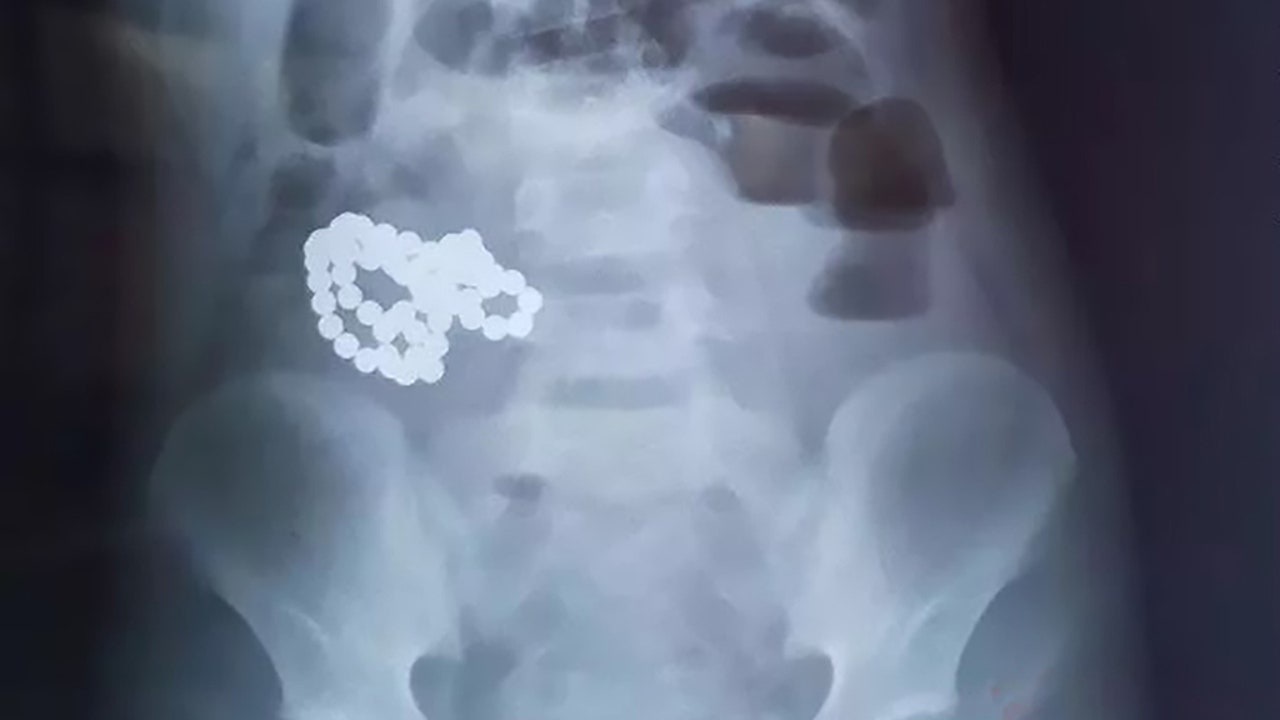

After ingesting the balls, the child didn’t experience any adverse effects until about six hours before he was admitted to the hospital,” Dr. Xu Bo, who treated the boy at the hospital located in China’s Heilongjiang Province, told AsiaWire. “In scans we found a cluster of high-density shadows. It looked like a necklace. I asked whether he had ever swallowed magnetic balls, and he said yes.”

The magnetic balls had stuck together in the boy's stomach to form what appeared to be a necklace. (AsiaWire)